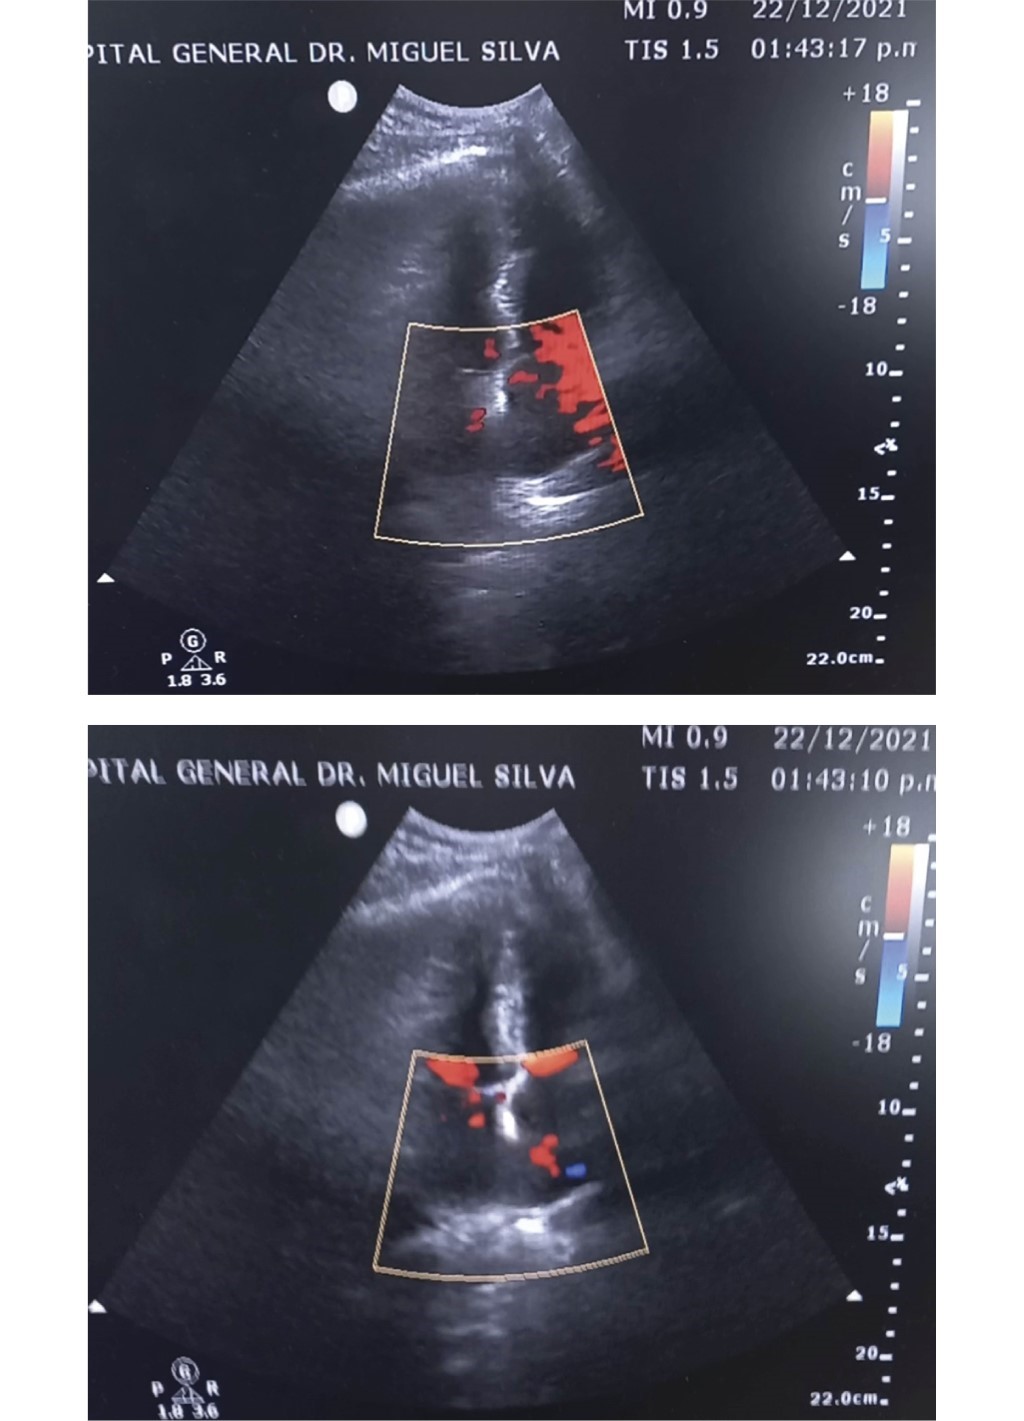

Interatrial septum rupture, a fatal complication of electrical burn: about a case

Introduction: the extent and severity of electrical injuries depend on the intensity of the electrical current –which is directly proportional to voltage and inversely proportional to resistance–, the entry point, the duration of contact, and the type of current, with alternating current being more dangerous than direct current.1,2 The heart is one of the most vulnerable organs to electrical current, which can cause arrhythmias, conduction disturbances, various electrocardiographic abnormalities, myocardial or valvular rupture, pericardial effusion, and structural changes in the coronary arteries and small myocardial vessels.2,3 Objective: to present a case report and review the literature on a patient with interatrial septum rupture secondary to an electrical burn, treated in the intensive care unit. Case report: a 54-year-old male patient presented with sudden onset of symptoms following a high-voltage electrical burn. His hemodynamic status deteriorated, prompting investigation into a possible cardiac cause. Conclusion: implementing an early echocardiogram protocol for patients with electrical burns could significantly impact mortality rates in these cases.

Figure 1

Figure 2